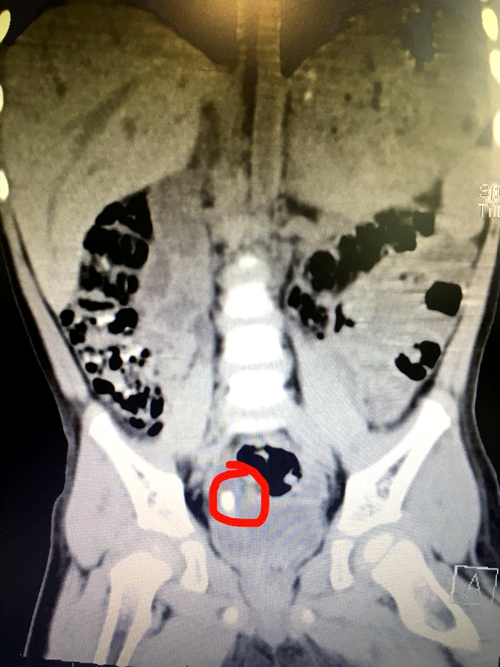

一周前,湘雅常德医院泌尿外科收治了一名来自慈利县刚满周岁的小宝宝——刚刚。据刚刚妈妈介绍,刚刚在半年前就反复出现血尿情况,在当地多次检查,几个月都未找到血尿的真正原因。辗转来到...